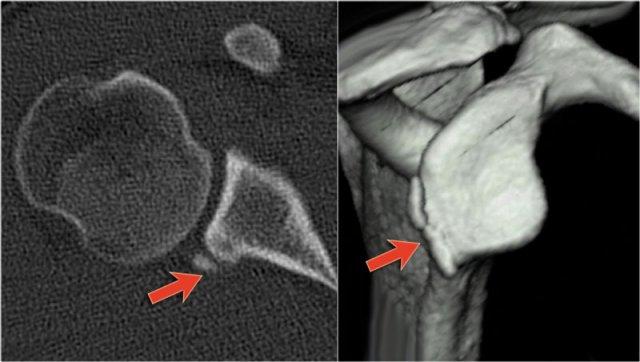

Các hình ảnh cho thấy một gãy xương Bankart kín đáo (mũi tên).

Trên tái tạo mặt phẳng chếch vành tai và mặt phẳng đứng dọc, mảnh gãy di lệch của bờ ổ chảo được thấy ở vị trí 3-6 giờ.

Trên hình ảnh mặt phẳng vành tai, quan sát thấy một khuyết xương Hill-Sachs lớn.

Đây là khuyết xương do hậu quả của sự va đập bờ ổ chảo vào chỏm xương cánh tay.

Tái tạo 3D của tổn thương Bankart xương lớn tại vị trí 2 – 6 giờ.